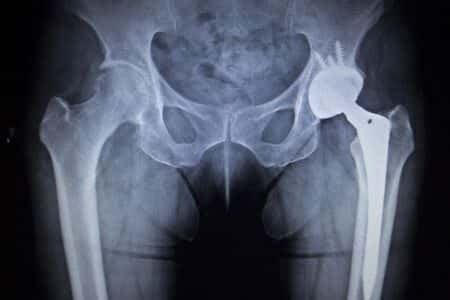

This case involves a 70 year-old woman with a history of rheumatoid arthritis who used the Zimmerman hip device after she fell at her home and dislocated her hip. After assessing her condition, the doctor decided a hip replacement was her best option. The operation went well and the patient was allowed to leave after four days. However, she soon started to experience pain and swelling in her hip area but did not inform her doctor until the pain became severe. A later evaluation showed she had developed metallosis since receiving the Zimmer hip replacement. She subsequently questioned the safety and regulations used for the Zimmer hip.